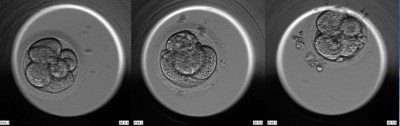

bitte um Beurteilung meiner drei verbleibenden Kryos. Die Linke und in der Mitte wurden an Tag 3 eingefroren als 8-Zeller. Die rechte wurde bis zur Blastozyste weiterentwickelt.

Ich habe drei Entwicklungsstadien aus dem Film abgebildet. 1. Foto 48 Stunden, 2. Foto 69 Stunden und letztes Bild nach 109 Stunden.

alle drei Embryonen haben an Tag 3 zeitgerechte und gute Strukturen

und somit ein gutes Potential, um zu entwicklungsfähigen BCs zu werden.

Den Embryo an d5 würde ich mit 1BB einstufen d.h. eine BC, deren Strukturen

beginnen, sich gut auszubilden und gute Voraussetzungen für die weitere Entwicklung zeigen.